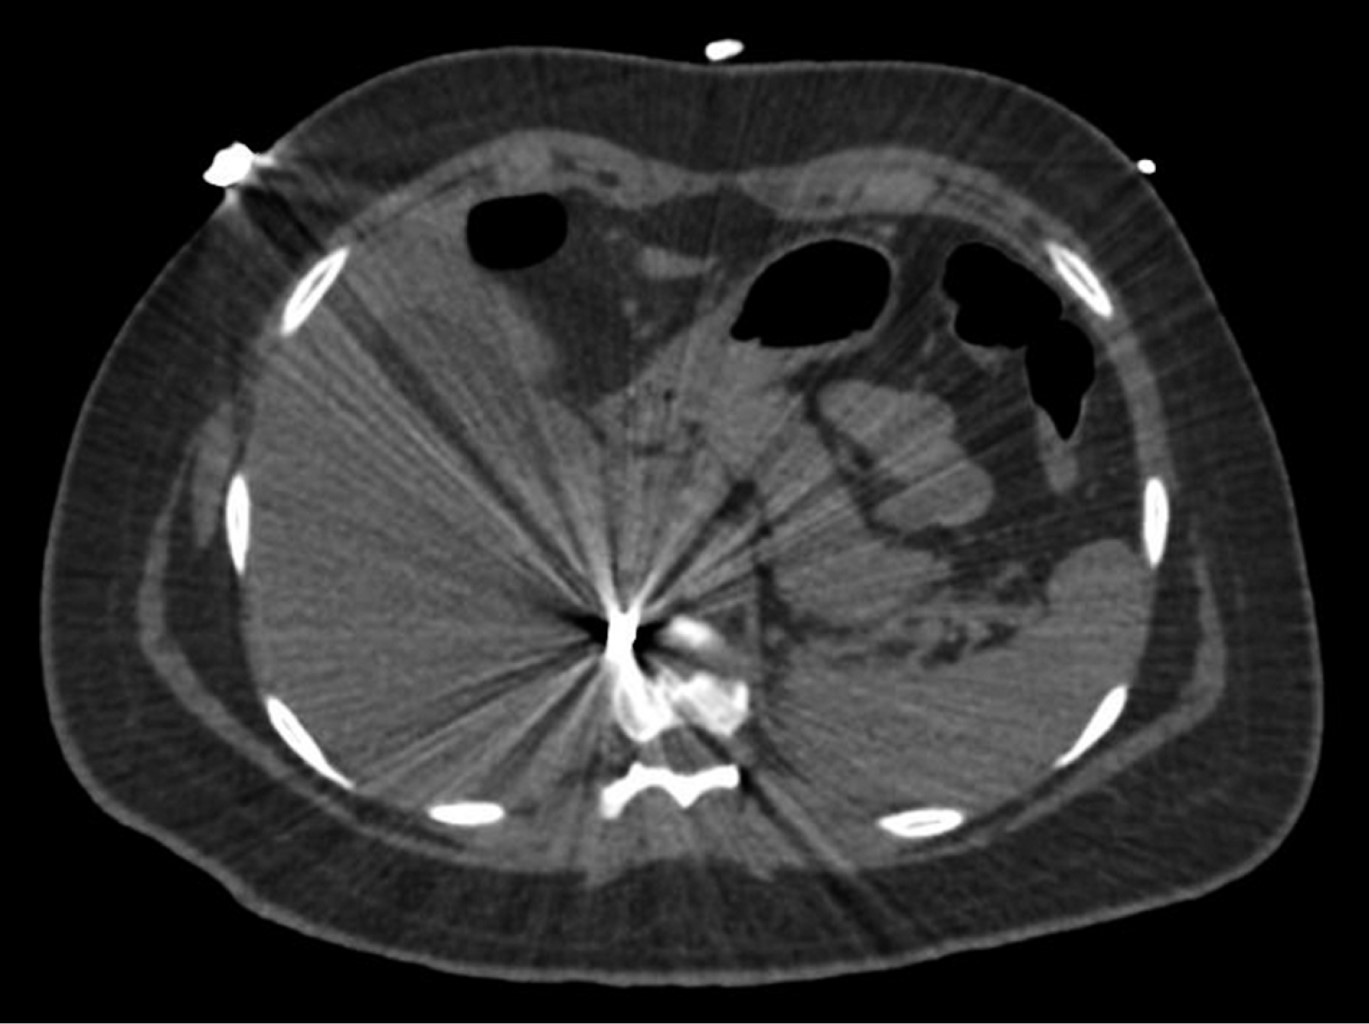

En la exploración física, sus signos vitales fueron los siguientes: frecuencia cardiaca: 74 latidos/minuto; tensión arterial: 98/67 mmHg; frecuencia respiratoria: 19/minuto, temperatura de 36 °C y saturación de oxígeno: 98%. En tórax presentaba un orificio de entrada de PAF en el cuadrante superior externo de la mama derecha (Figura 1), los campos pulmonares estaban bien ventilados. El abdomen era plano, con peristalsis, blando y sin dolor a la palpación. La biometría hemática reportó lo siguiente: hemoglobina: 12.8 g/dl, hematocrito 36.4% y leucocitos: 6,400/ml. La radiografía de tórax descartó neumotórax (Figura 2). Una TC de tórax y abdomen mostró un cuerpo extraño metálico alojado en la línea parasagital derecha a nivel de la doceava vértebra torácica (Figura 3), sin lesión pulmonar ni diafragmática (Figuras 4 y 5); en abdomen se observó un trayecto por PAF con lesión hepática grado IV de 12 cm por 2.3 cm en los segmentos IV, VII y VIII de Couinaud (Figura 5), líquido libre escaso, sin lesión de ningún otro órgano (Figuras 3, 5 y 6). Veinticuatro horas después se le realizó una TC de control, evidenciando la lesión hepática sin colección subcapsular ni extravasación activa a la aplicación del medio de contraste, sin aumento del líquido libre. Ante la correlación de estos hallazgos con la estabilidad clínica, se egresó a la paciente al cuarto día de su ingreso. Sin complicaciones un mes después de su alta.

Figura 3